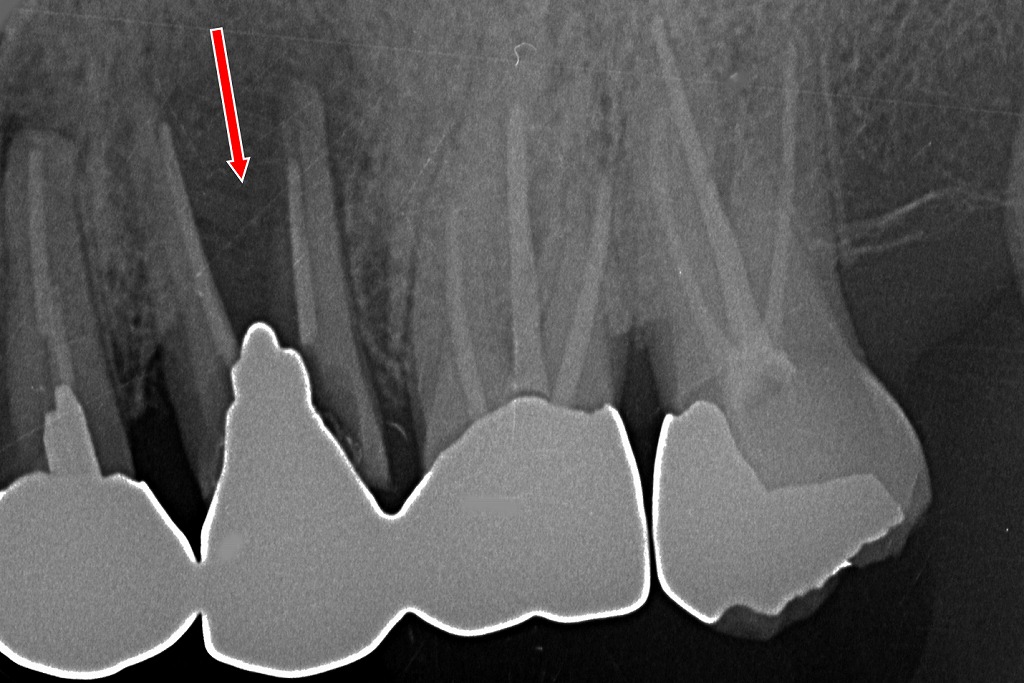

上顎5番の歯根破折(メタルコア)

赤い矢印で示された上顎5番の根管内には、メタルコアが装着されています。その周囲には**歯根破折の透過像(黒く抜けて見える部分)**が確認できます。

観察ポイント

- 垂直性の透過像

歯根に沿うように黒い線状の透過像が見られ、これは典型的な歯根破折の所見です。 - メタルコアの存在

メタルコアは硬く、力が集中しやすいため、長期的には歯根破折のリスクが高まります。 - 周囲歯槽骨の吸収

破折に伴い、周囲の骨が部分的に吸収しています。